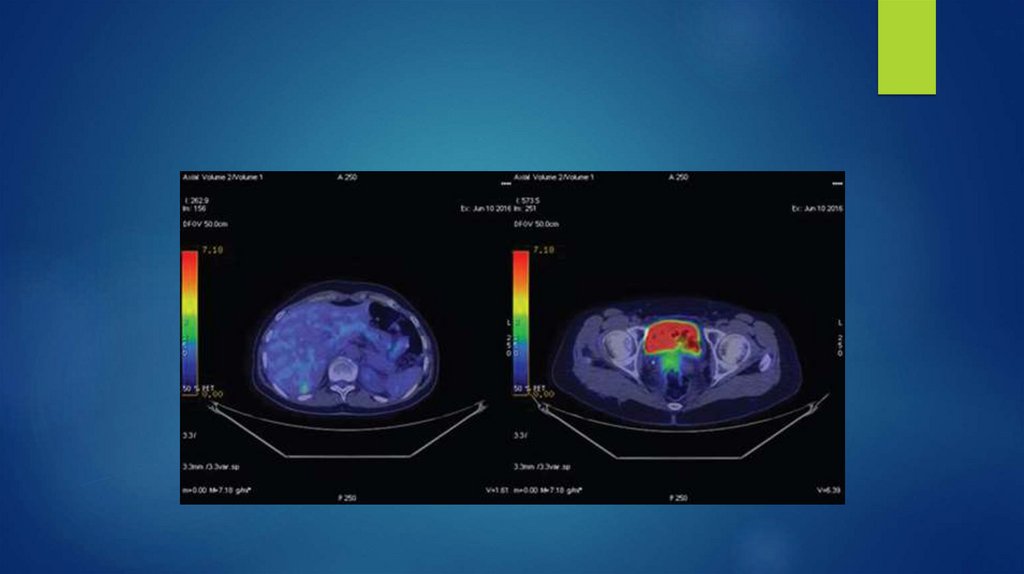

84. Позитронно-эмиссионная томография (ПЭТ)

- данный метод основан на регистрации пары гамма-квантов,

возникающих при аннигиляции позитронов с электронами.

Позитроны возникают при позитронном бетараспаде радионуклида, входящего в

состав радиофармпрепарата, который вводится в организм

перед исследованием

Позитронно-излучающие изотопы:

Углерод-11

Азот-13

Кислород-15

Фтор-18